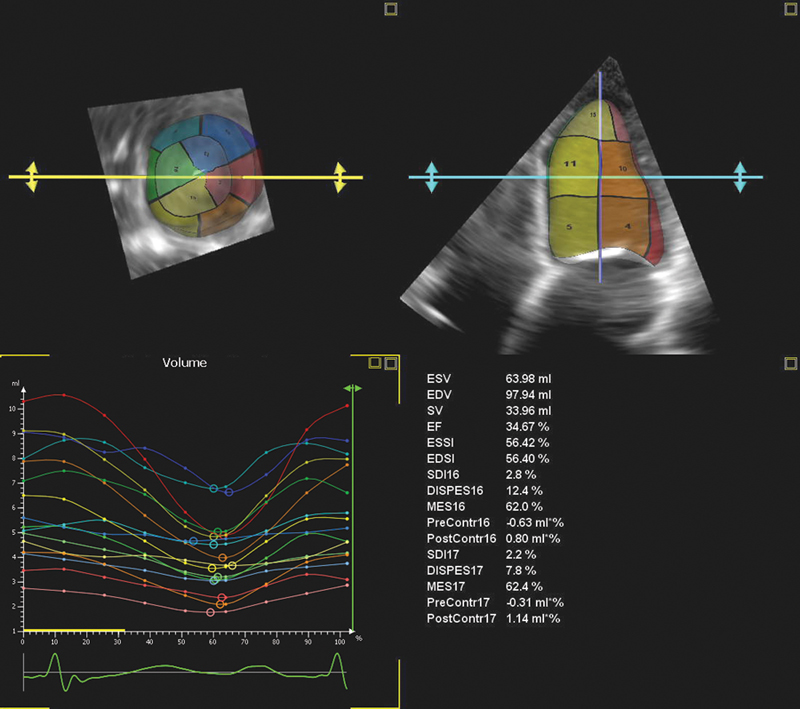

فحوصات تشخيصية لبعض امراض القلب والشرايين التاجية